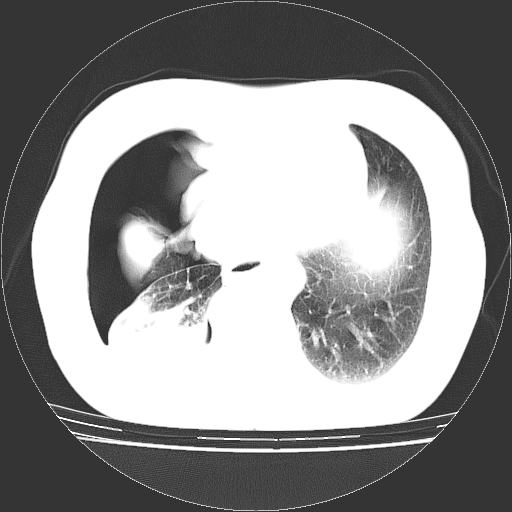

以下是引用zhangzhongshou在2008-3-22 12:52:00的发言:[br]1、右侧液气胸。[br]2、腹水。建议进一步检查。

以下是引用鲁巨ct在2008-3-22 14:10:00的发言:[br]1、右侧液气胸,右中下叶节段性不张。[br]2、腹水,建议上腹部ct检查

以下是引用zjzjr在2008-3-22 17:19:00的发言:[br]1、右侧液气胸,右下叶节段性不张。[br]2、腹水,建议上腹部ct检查